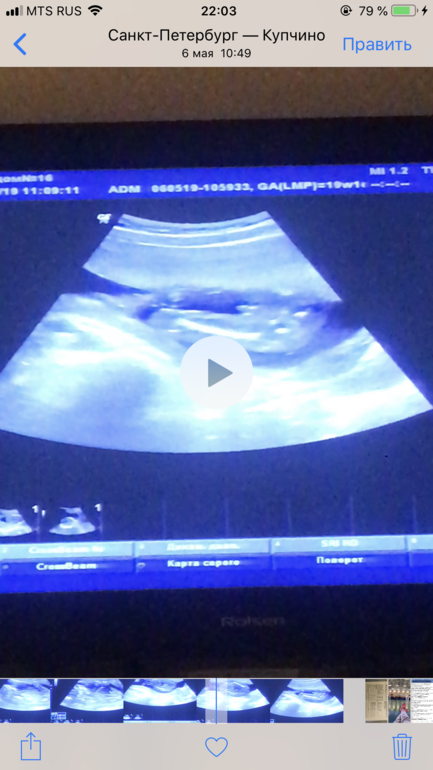

Мальчик ли?)

Видимо вот сюда

а вертикальная линия это бедро?

Горизонтальная линия бедренная кость)

ой, да, горизонтальная. Вот теперь и я вижу))

Конечно пацанчик))) перчик уже солидный))) 😅 😅 😅 😅

Это мальчик 100% 😁

Пацан. У девочек там пусто)

Точно мальчик!

Конечно мальчик, там вон причендал уже видно :)